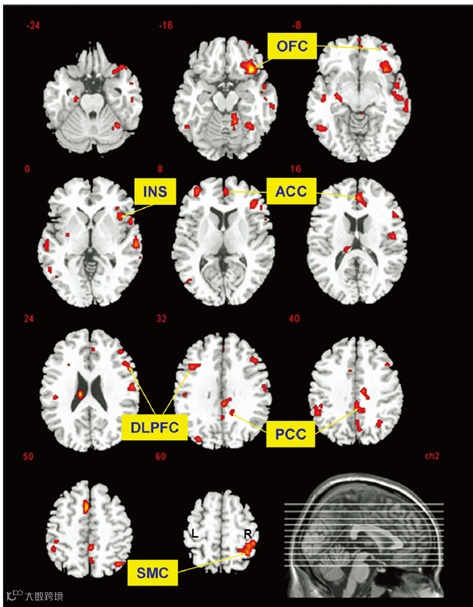

结果发现,与休息状态相比,跑步 30 分钟后,跑步者大脑中阿片类物质(不知道什么是阿片类物质的可以自行百度哦)和它们受体的结合更加活跃了!